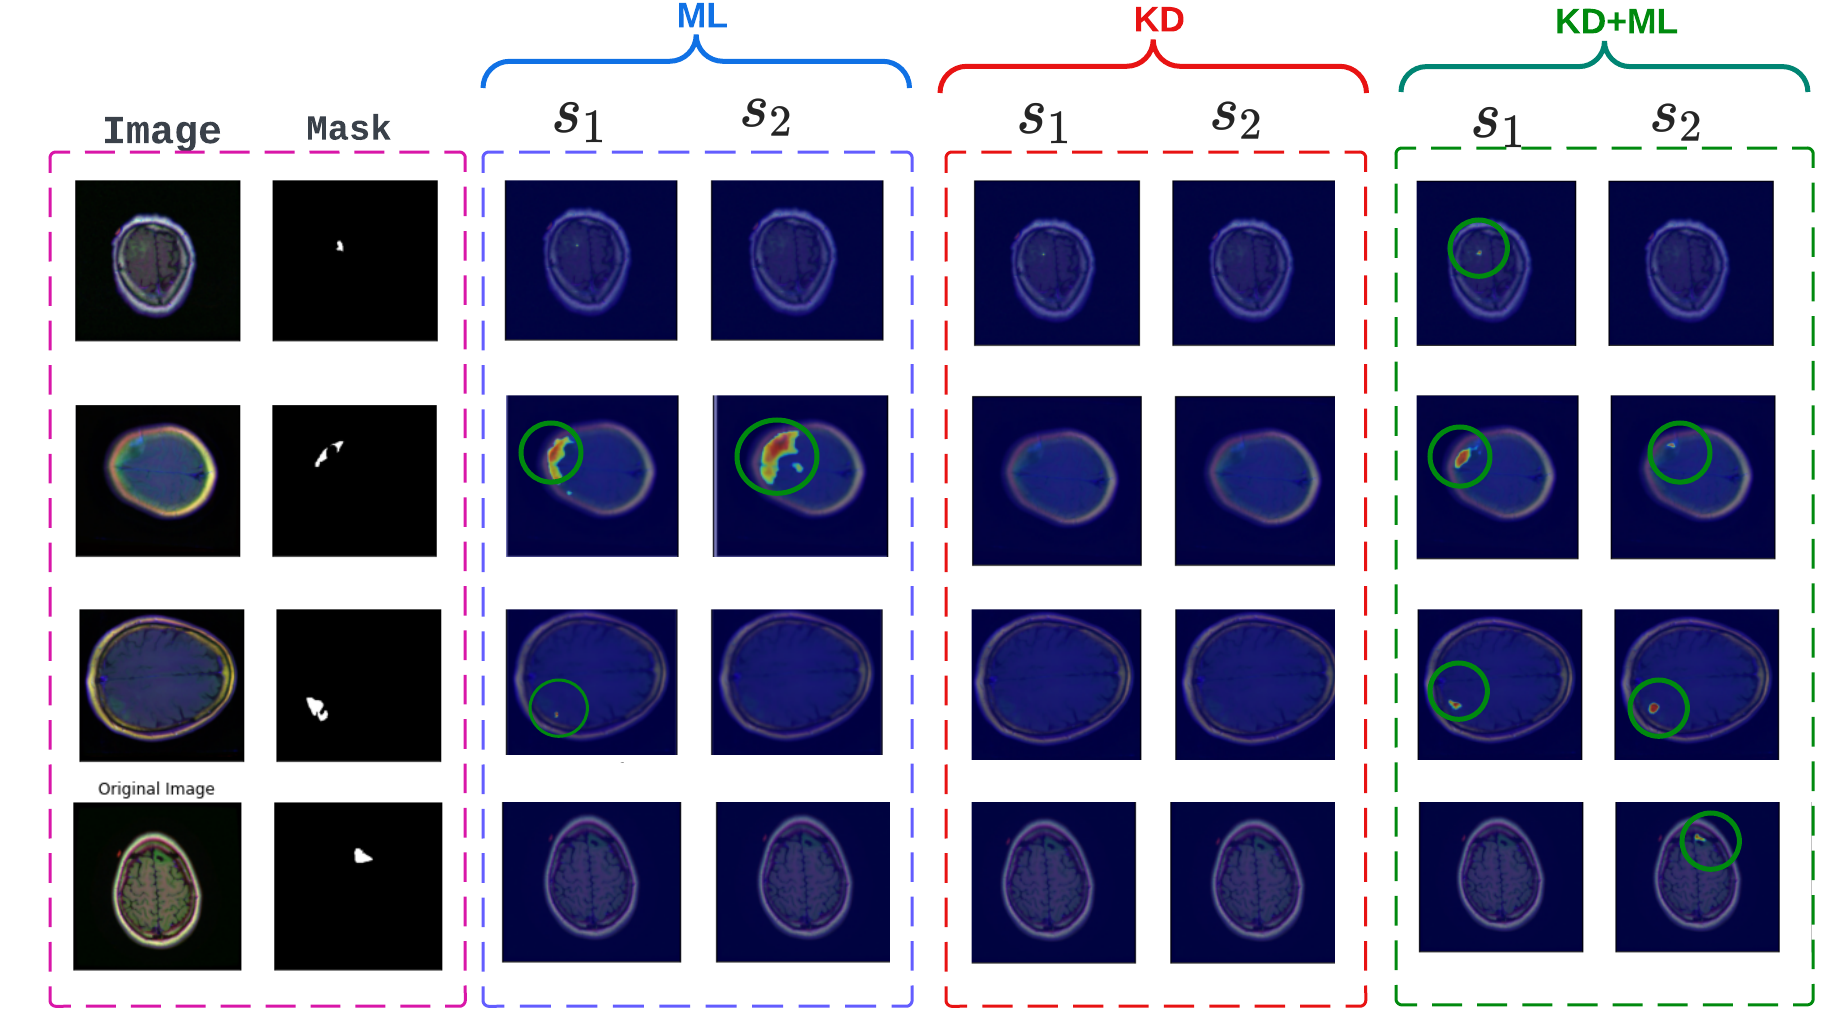

To better appreciate the significance of the proposed approach, we provide a qualitative comparison of different distillation techniques and information-sharing strategies using individual student predictions for some hard-to-segment test samples. Figure 4 extensively compares all the models for three test samples. In general, it can be observed that KD-only and ML-only models struggle with the segmentation of small regions of interest. It can also be noticed that for conventional models, only one of the two students manages to predict these small regions. In our proposed approach, an ensemble of student predictions is used for the final predictions, facilitating the student networks to consistently predict the region of interest and yield optimal performance. Moreover, student networks trained using a diverse knowledge paradigm demonstrate a superior ability to discern finer structures compared to other models.

We demonstrate the importance of combining KD with ML by comparing all models trained with a knowledge diversification paradigm in Figure 5. It can be noticed that the combined KD + ML model successfully detects these small regions of interest from these hard sample images where KD-only and ML-only models fail. Similarly, to underscore the significance of knowledge diversification over other learning strategies, we show sample predictions from the combined KD + ML model trained with V1 (predictions only), V2 (features only), and a diverse knowledge paradigm, V3 (both predictions and features) (Figure 9 in the supplementary material) where we observe that the V3 strategy helps detect small and fine regions of interest better than V1 and V2.

5.4 Explainability